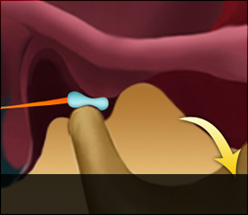

디스크 전방전위2

입을 다물고 있는 상태

입을 열고 있는 상태

입을 열어도 디스크가 제자리로

돌아가지 못하는 경우